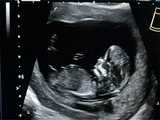

5.B超检查。通过B超检查胚胎发育存在异常,也可能是发生了胚胎停育的情况。